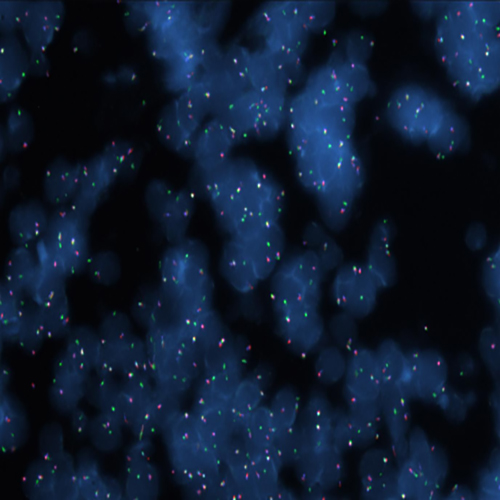

Hybridization of MYC TC break probe to a tissue section showing abarrant pattern (1GBR1G1BR).

IVD MYC (8q24) Break (tissue)

Rearrangements of the proto oncogene MYC c-myc) have been consistently found in Burkitt's lymphoma tumor cells. In cases with the common t(8;14) chromosomal translocation, the MYC gene is translocated to chromosome 14 and rearranged with the immunoglobulin heavy chain genes; the breakpoint occurs 5' to the MYC gene and may disrupt the gene itself. In Burkitt's lymphoma showing the variant t(2;8) or t(8;22) translocations, the genes coding for the k and l immunoglobulin light chain are translocated to v-myc avian myelocytomatosis viral oncogene homolog (MYC or c-myc) chromosome 8. The MYC (8q24) Break probe is optimized to detect rearrangements involving the 8q24 locus in a triple-color, split assay on formalin fixed paraffin embedded tissue.